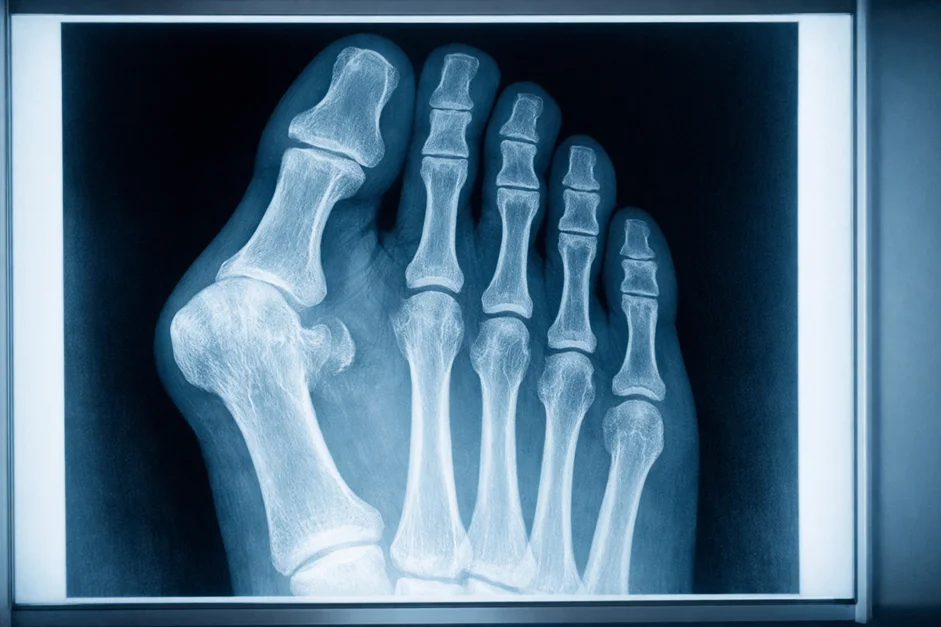

- Рентгенография. Назначается для исключения костной патологии, переломов, трещин и признаков артроза. Сама бурса на рентгене не видна, но метод важен для оценки сопутствующих деформаций — вальгуса, деформации Тейлора, изменений плюсневых костей.